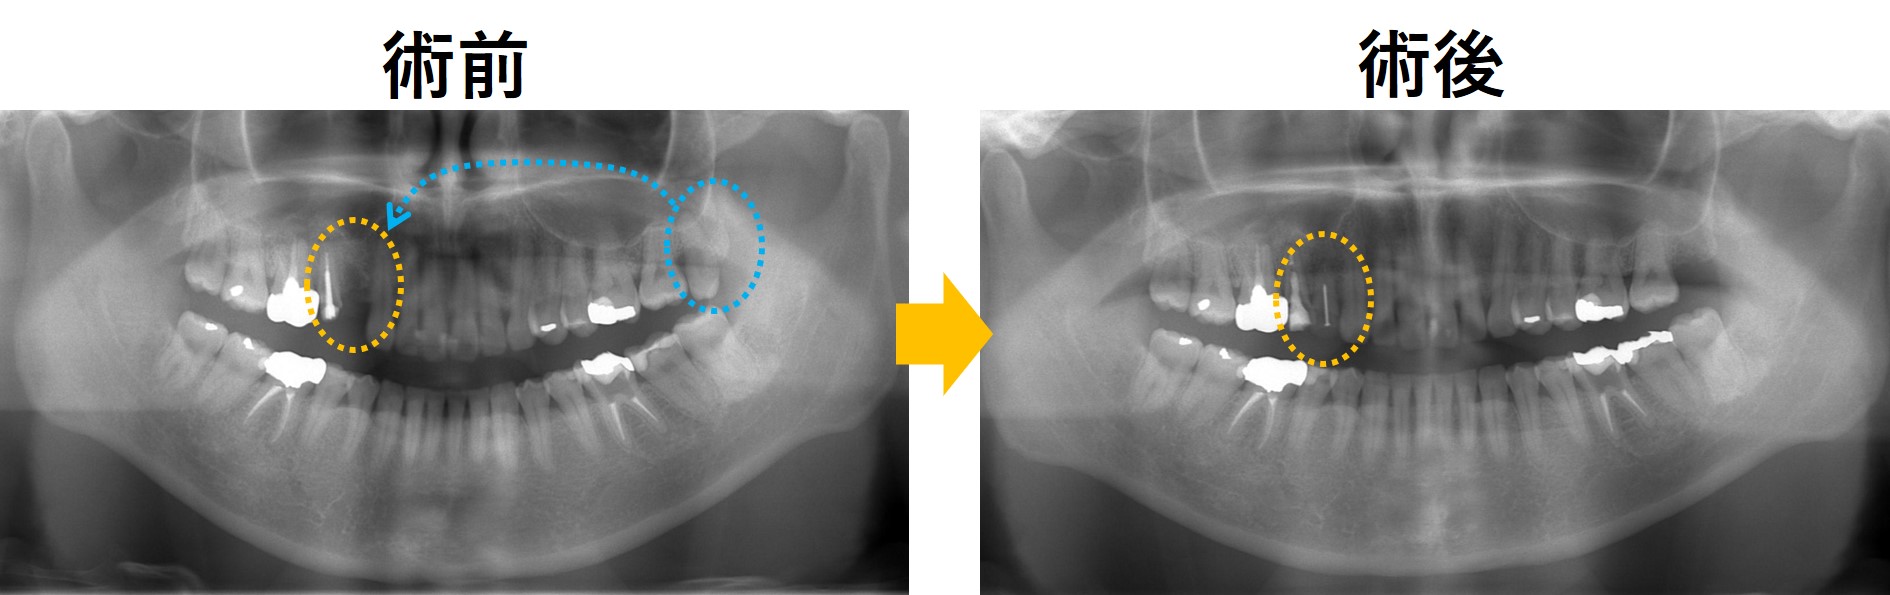

レントゲン写真です。患者さんの同意を得てHPにアップさせていただいています。

左写真は術前です。オレンジ部分の歯が抜けています。青〇は親知らずです。この親知らずを歯が抜けているオレンジ部分に移植する計画としました。

右写真が術後1年後になります。